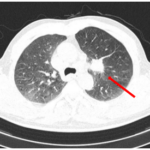

CASE LÂM SÀNG Điều trị bệnh nhân mắc đồng thời hai loại ung thư: Ung thư phổi và ung thư tuyến tiền liệt

CASE LÂM SÀNG Điều trị bệnh nhân mắc đồng thời hai loại ung thư: Ung thư phổi và ung thư...